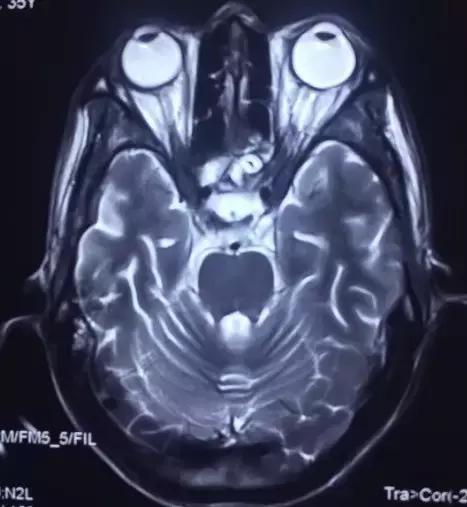

菅老师您好,打扰您了,今天下午做的磁共振,您看一下。

(部分图片)

核磁共振看的还可以,这个病人一点儿意识也没有吗?抽搐的话,脑电图对诊断应该有所帮助。